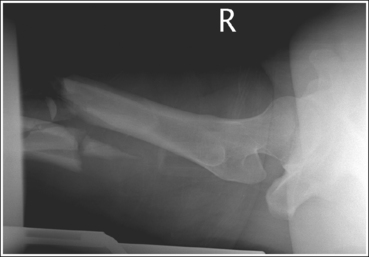

• Positioning for fracture. For a patient with a known or suspected fracture who is unable to position both the ankle and knee into an AP projection simultaneously, position the joint closer to the fracture in the truer position. When the fracture is situated closer to the ankle, the ankle should meet the preceding requirements for a true distal lower leg AP projection (see Image 50). When the fracture is situated closer to the knee, the knee should meet the requirements for accurate positioning for a proximal lower leg AP projection. Depending on the degree of tibial and fibular rotation at the fracture site, the other joint may or may not be accurately positioned for an AP projection.

IMAGE 50